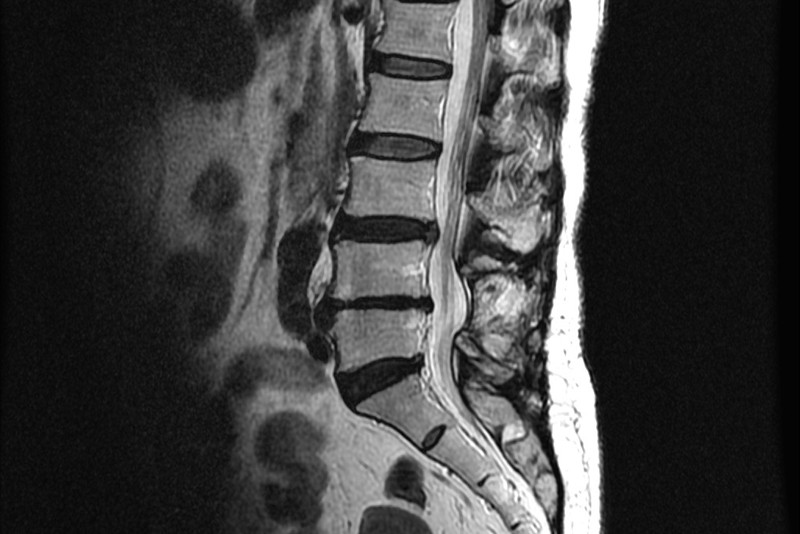

서울대 재활의학과 교수님이 쓴 책의 내용인데 1주일에 20km 이상을 달리는 사람과 운동은 하지 않는 사람들을 비교해 봤을 때, MRI 영상에서 달리기를 꾸준히 하는 사람들이 허리디스크가 두꺼웠고 그 속의 수분 함유하고 있는 분량이 높았다는 내용이 있었습니다.